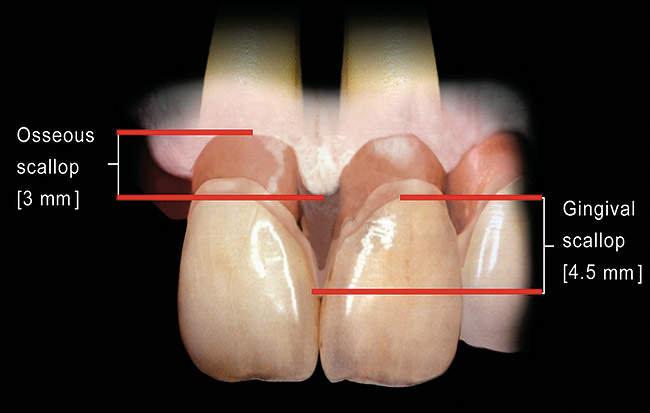

Figure 10  In these adjacent implants placed in the central and lateral positions, note the excellent interproximal bone but minimal interimplant distance.

Figure 10

1. It is difficult to place adjacent implants in a central and lateral position, or a lateral and cuspid position, and have 3 mm between the platform of the implants. This leaves a high risk of losing the interproximal crest of bone between the implants over time, with subsequent loss of papillary height (Figure 10, Figure 11, Figure 12 and Figure 13).